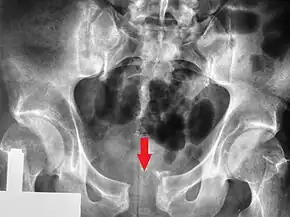

Le bassin est une structure osseuse formant un anneau en entonnoir, particulièrement stable dans son intégrité. Les éléments osseux sont maintenus par deux systèmes principaux de ligaments : en avant celui de la symphyse pubienne, et en arrière celui de l'articulation sacro-iliaque, les deux réunis par les ligaments du plancher pelvien.

Une fracture de cet anneau osseux est susceptible de déstabiliser l'ensemble, d'autant plus qu'elle est multiple, avec des lésions ligamentaires et des structures anatomiques situées dans ou en dehors du bassin. Des forces très importantes sont nécessaires : par exemple il faut une force d'au moins 800 kg pour produire une rupture des ligaments sacro-iliaques[8].

En fonction des forces appliquées sur le bassin, trois mécanismes sont décrits :

- La compression antéro-postérieure : elle endommage d'abord les ligaments de la symphyse pubienne, suivi de la rupture des ligaments du plancher pelvien (ligaments sacro-iliaques), et enfin fracture des deux cadres obturateurs.

- La compression latérale : elle se traduit par des fractures du cadre obturateur, de l'aile iliaque (dite fracture de Malgaigne), ou d'un aileron sacré (dite fracture de Voillemier[9]).

- La compression verticale : un choc asymétrique sur une moitié d'un pelvis (chute de hauteur ou collision à grande vitesse) peut entrainer un cisaillement avec déplacement vertical du même type de lésions rencontrées dans les compressions latérales.

Un quatrième mécanisme est dit « complexe ou combiné », lorsqu'il associe plusieurs des mécanismes précédents.